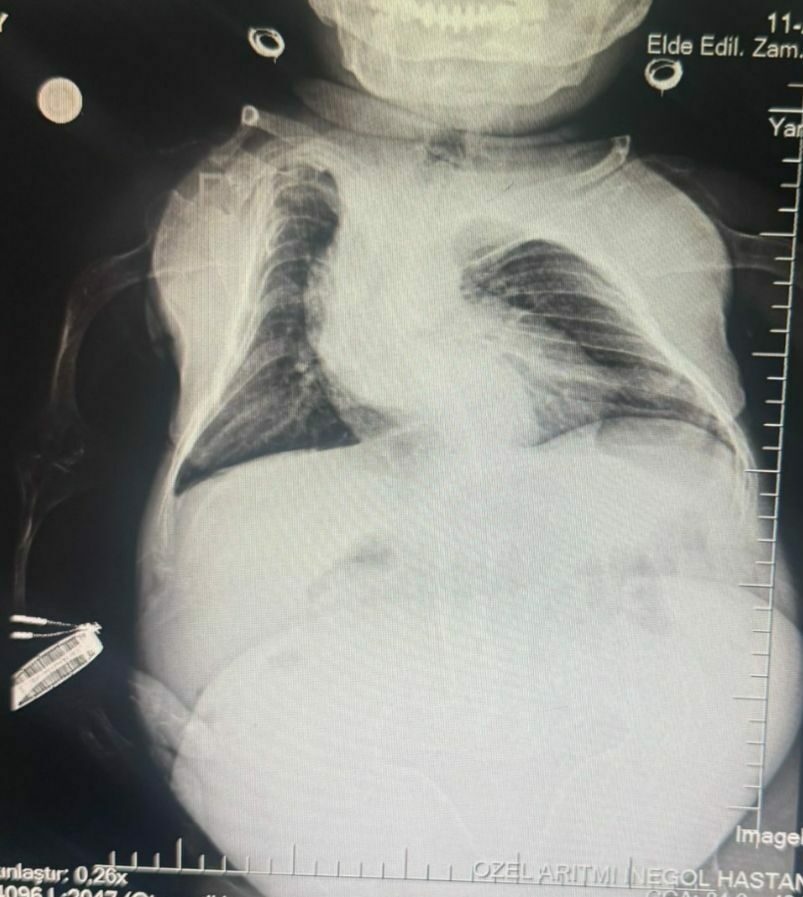

Kadın Hastalıkları Uzmanı Mustafa Kır, “Hastamızda 20 santimlik tümör vardı, kistlik yapıda. Onu başarılı bir operasyonla çıkarttık” derken, operasyonun başarılı geçtiğini söyleyen Anestezi Doktoru Mahmut Gül, operasyon sürecini şu sözlerle anlattı: “Hastamız, 30 yaşında, 80 santimetre boyunda, 24 kilo ağırlığında bir kardeşimiz. Kendisinin yumurtalıklarında kist olduğu için ameliyat olması gerekti. Biz bu ameliyatta hastamıza önce büyük bir damar yolu açtık kasıktan. Çünkü damar yolunun çok önemi var ve daha sonrasında ameliyat sırasında belinden uyuşturduk ve ameliyatı sorunsuz bir şekilde, belden uyuşturmayla, hastamız uyanık bir şekilde tamamladık. Hastadan 3 kilo kist çıktı. Öncesinde 24 kilo olan hastamız ameliyat sonrasında 21 kilo ile şifalı bir şekilde serviste yatıyor. Başarılı bir operasyondu.”